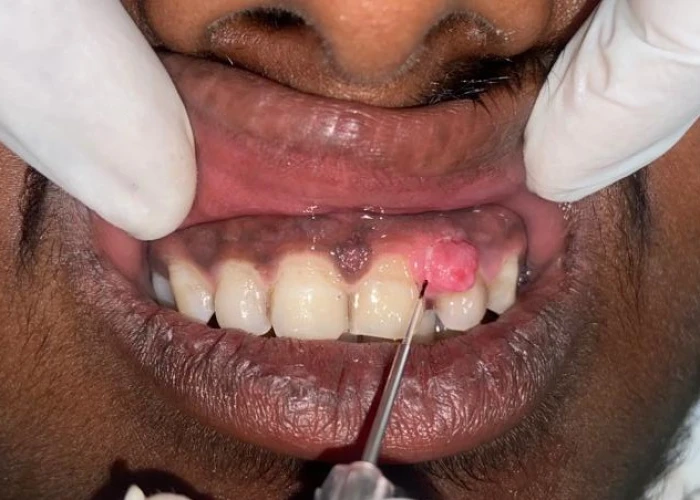

3. Malignant Oral disease.

Oral Medicine & Radiology is concerned with diagnosis and medical management of diseases specific to the oral & maxillofacial structures, management of oral manifestations of systemic diseases, management of behavioral disorders, and dental treatment of medically compromised patients. It deals with the diagnostic intraoral and extraoral imaging of maxillofacial structures by both conventional and digital methods. It further includes Forensic Odontology and also promotes tobacco cessation.

Oral Medicine & Radiology is the Gateway to Dentistry. It provides high quality clinical diagnostic training for management of potentially malignant disorders and oral cancer, medical emergencies, training in tobacco cessation, chair side investigative procedures, Basic Life Support, and LASER, apart from general dentistry. It also provides exposure in forensic odontology, specialized training in diagnostic digital imaging.